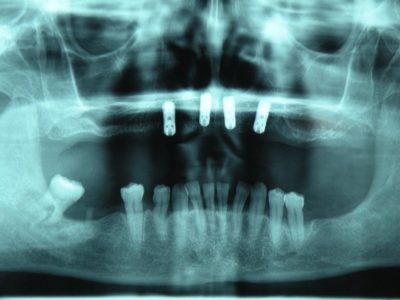

An implant is actually the replacement for a root of a tooth. It is a screw of precisely defined size that is installed in the bone of the jaw. It is made of titanium, a precious metal, the only one compatible with human bones. The decision of the installment of the implant is made on the basis of a digital orthopan and a computed tomography (CT), i.e. the scan of the jaw. One or more teeth can be replaced with the help of implantology, and the implant is the base, or, rather, the carrier of the prosthetic replacement. Prosthesis and dental bridges can be attached to the implants, but one implant can also replace only one tooth if only that one is missing from the teeth row.

Dental bridges on implants are used to lower the loading from the individual implant, i.e. in the cases when the patient misses more than one tooth. The process of installation of dental bridges on the implants differs from the one of the prosthesis installation. Namely, the implantation and the time necessary for the doctor to assure that the implants are completely integrated in the bones, follows the implant impression making and the installation of the upgrades (which „imitate“ the tooth). Dental bridges are installed on those upgrades.